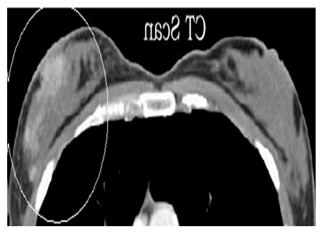

| CT-Scans | High | Precise | Can cause allergic reactions, comparably cost | ![]() |